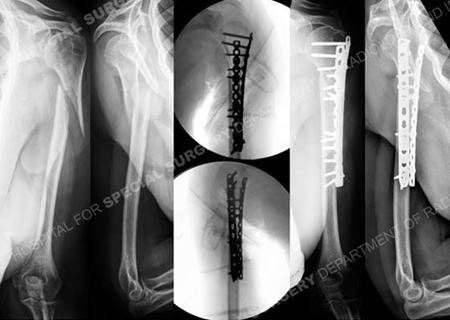

Pre-operative anteroposterior (AP) and lateral radiographs (left images) of an AO/OTA type 12-A2.1 proximal humeral nonunion, intraoperative fluoroscopic AP and lateral images (center images) demonstrating acceptable reduction and placement of hardware and AP and lateral radiographs (right images) 14 months following fracture surgery revealing a healed proximal humerus nonunion.

A 64-year-old female sustained a left-sided proximal humerus fracture (AO/OTA Type 12-A2.1) and was initially treated at an outside hospital with a functional fracture brace. She was referred to David L. Helfet, MD at the Orthopedic Trauma Service of Hospital for Special Surgery 4 months following her fracture and radiographs revealed a nonunion. Open reduction and internal fixation was performed with placement of a locking plate and reconstruction plate in a 90-90 orientation with placement of supplemental bone graft and placement of interfragmentary lag screws. She returned at regular follow-up intervals and healed uneventfully at 3 months following fracture surgery. At her latest follow-up visit at 14 weeks she has an excellent range of motion and has returned to all pre-injury activities.